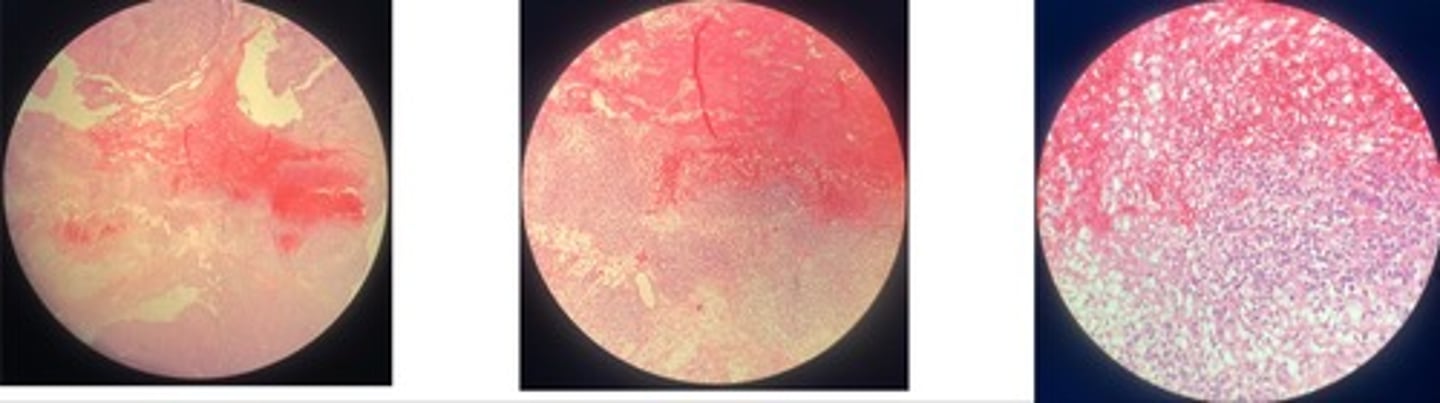

Contagious Bovine Pleuropneumonia (CBPP)

- fibrous pneumonia = acute, red, grey (increase neutrophils), resolution

- area of necrosis w/ bv @ centre + inflam cells surrounding

- marginal organisation…. granulation grows to surviving lobes

Equine Infectious Anemia (EIA)

- necrosis of central lobes

- congestion of c.v + sinuses

- hemosiderin + inflam cells in triad

- hyperplasia of Browicz-Kupfur cells